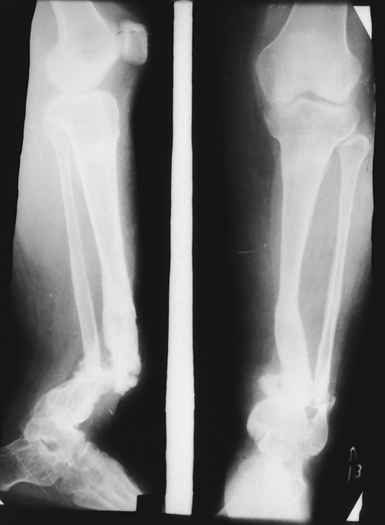

Женщина 28 лет, пошедшая 13 предыдущих оперативных вмешательств по-поводу ВПБ имела 9 см. укорочения.

На первом этапе аппаратом Илизарова закрыто устранена деформация голени.

На втором этапе произведёно освежение краёв костных фрагментов б/б и м/б костей с приданием проксимальному фрагменту б/б кости впалой, а дистальному выпуклой формы, открытие канала проксимального фрагмента и погружной остеосинтез, а также остеотомия б/б кости в в/3 и м/б кости на границе с/3 и н/3 голени. Больной проводился одновременный бифокальный компрессионно-дистракционный остеосинтез. Достигнуто 11 см. удлинение и сращение ВПГ.